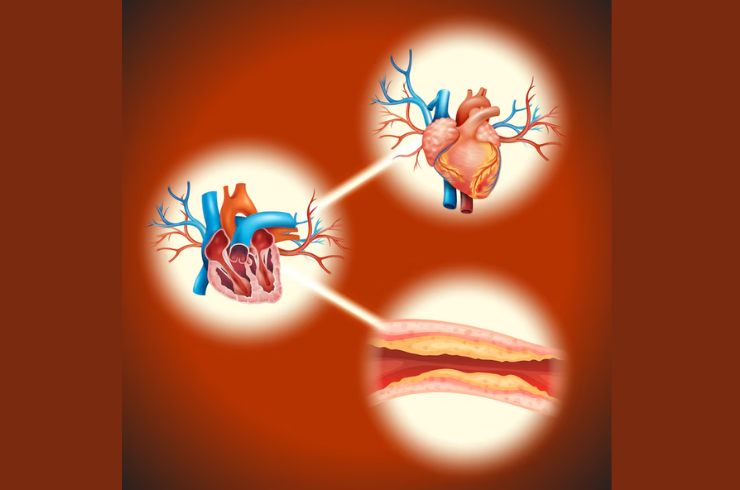

Coronary Artery Disease (CAD)

We address coronary artery issues through advanced interventions and treatments aimed at improving blood flow and reducing the risk of heart attacks and related conditions.